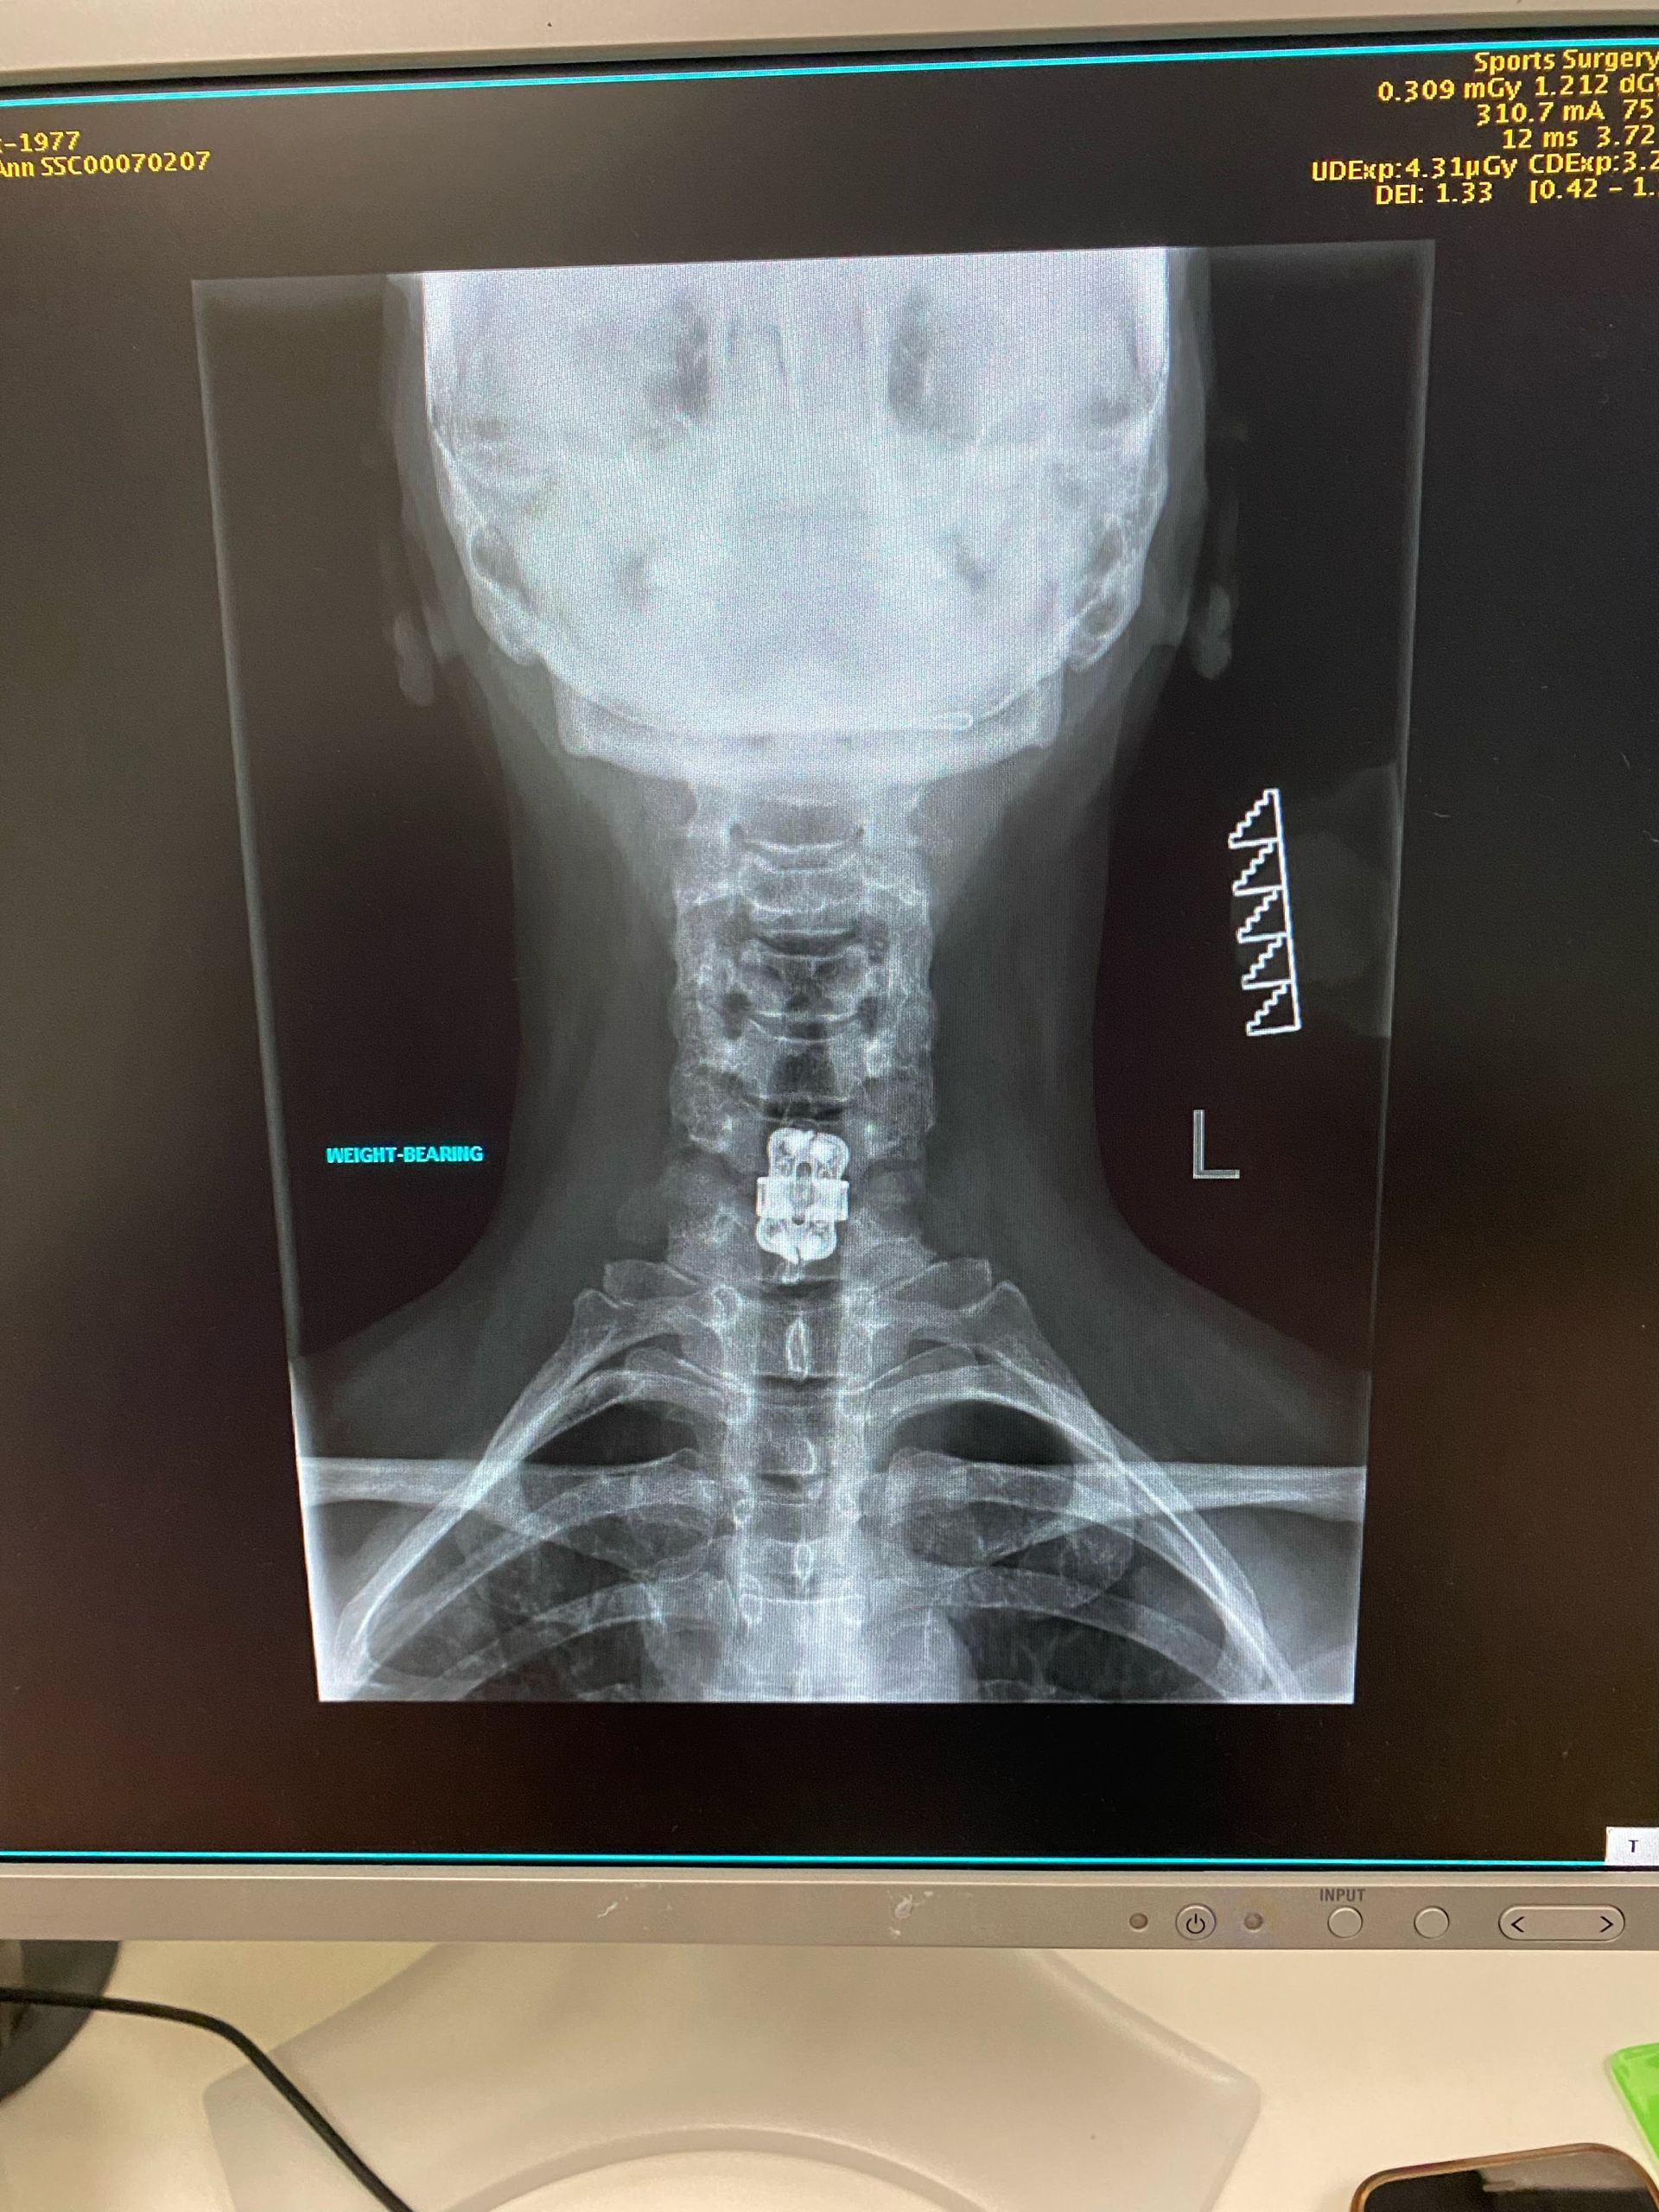

Last year I visited Mr Kelleher again with very bad neck and shoulder pain. He was able to arrange an MRI at short notice and, on foot of the MRI he explained that I needed another fusion, this time in my cervical spine, C6/C7. I trust Mr Kelleher so I was happy to proceed. After my surgery I had some pain in my neck and in my lower back so Mr Kelleher sent me to radiology for emergency MRI’s and once he saw there was no post surgical issues he sent Mr Tamilnani to see me. Mr Tamilnani set out a regime of medication for me to take when I went home which would keep my pain levels at bay. He also came to see me each day I was in the hospital.